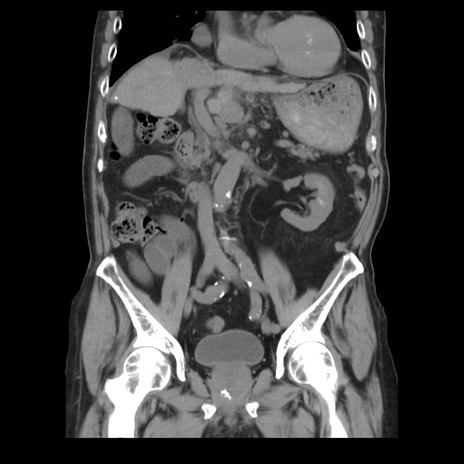

症例21(冠状断像)

【症例】70歳代男性

【主訴】腹痛

【現病歴】肝硬変・肝細胞癌にてかかりつけの方。約9時間前に食後より腹痛出現。症状が徐々に増悪し、嘔吐出現したため来院。

【既往歴】肝硬変、肝細胞癌(RFA、TACE後)

【身体所見】意識清明、表情苦悶様、BT 36℃、BP 129/78mmHg、P 88bpm、SpO2 97%(RA)、右上腹部から心窩部にかけて圧痛あり、反跳痛なし、筋性防御あり。

【データ】WBC 5800、CRP 0.16